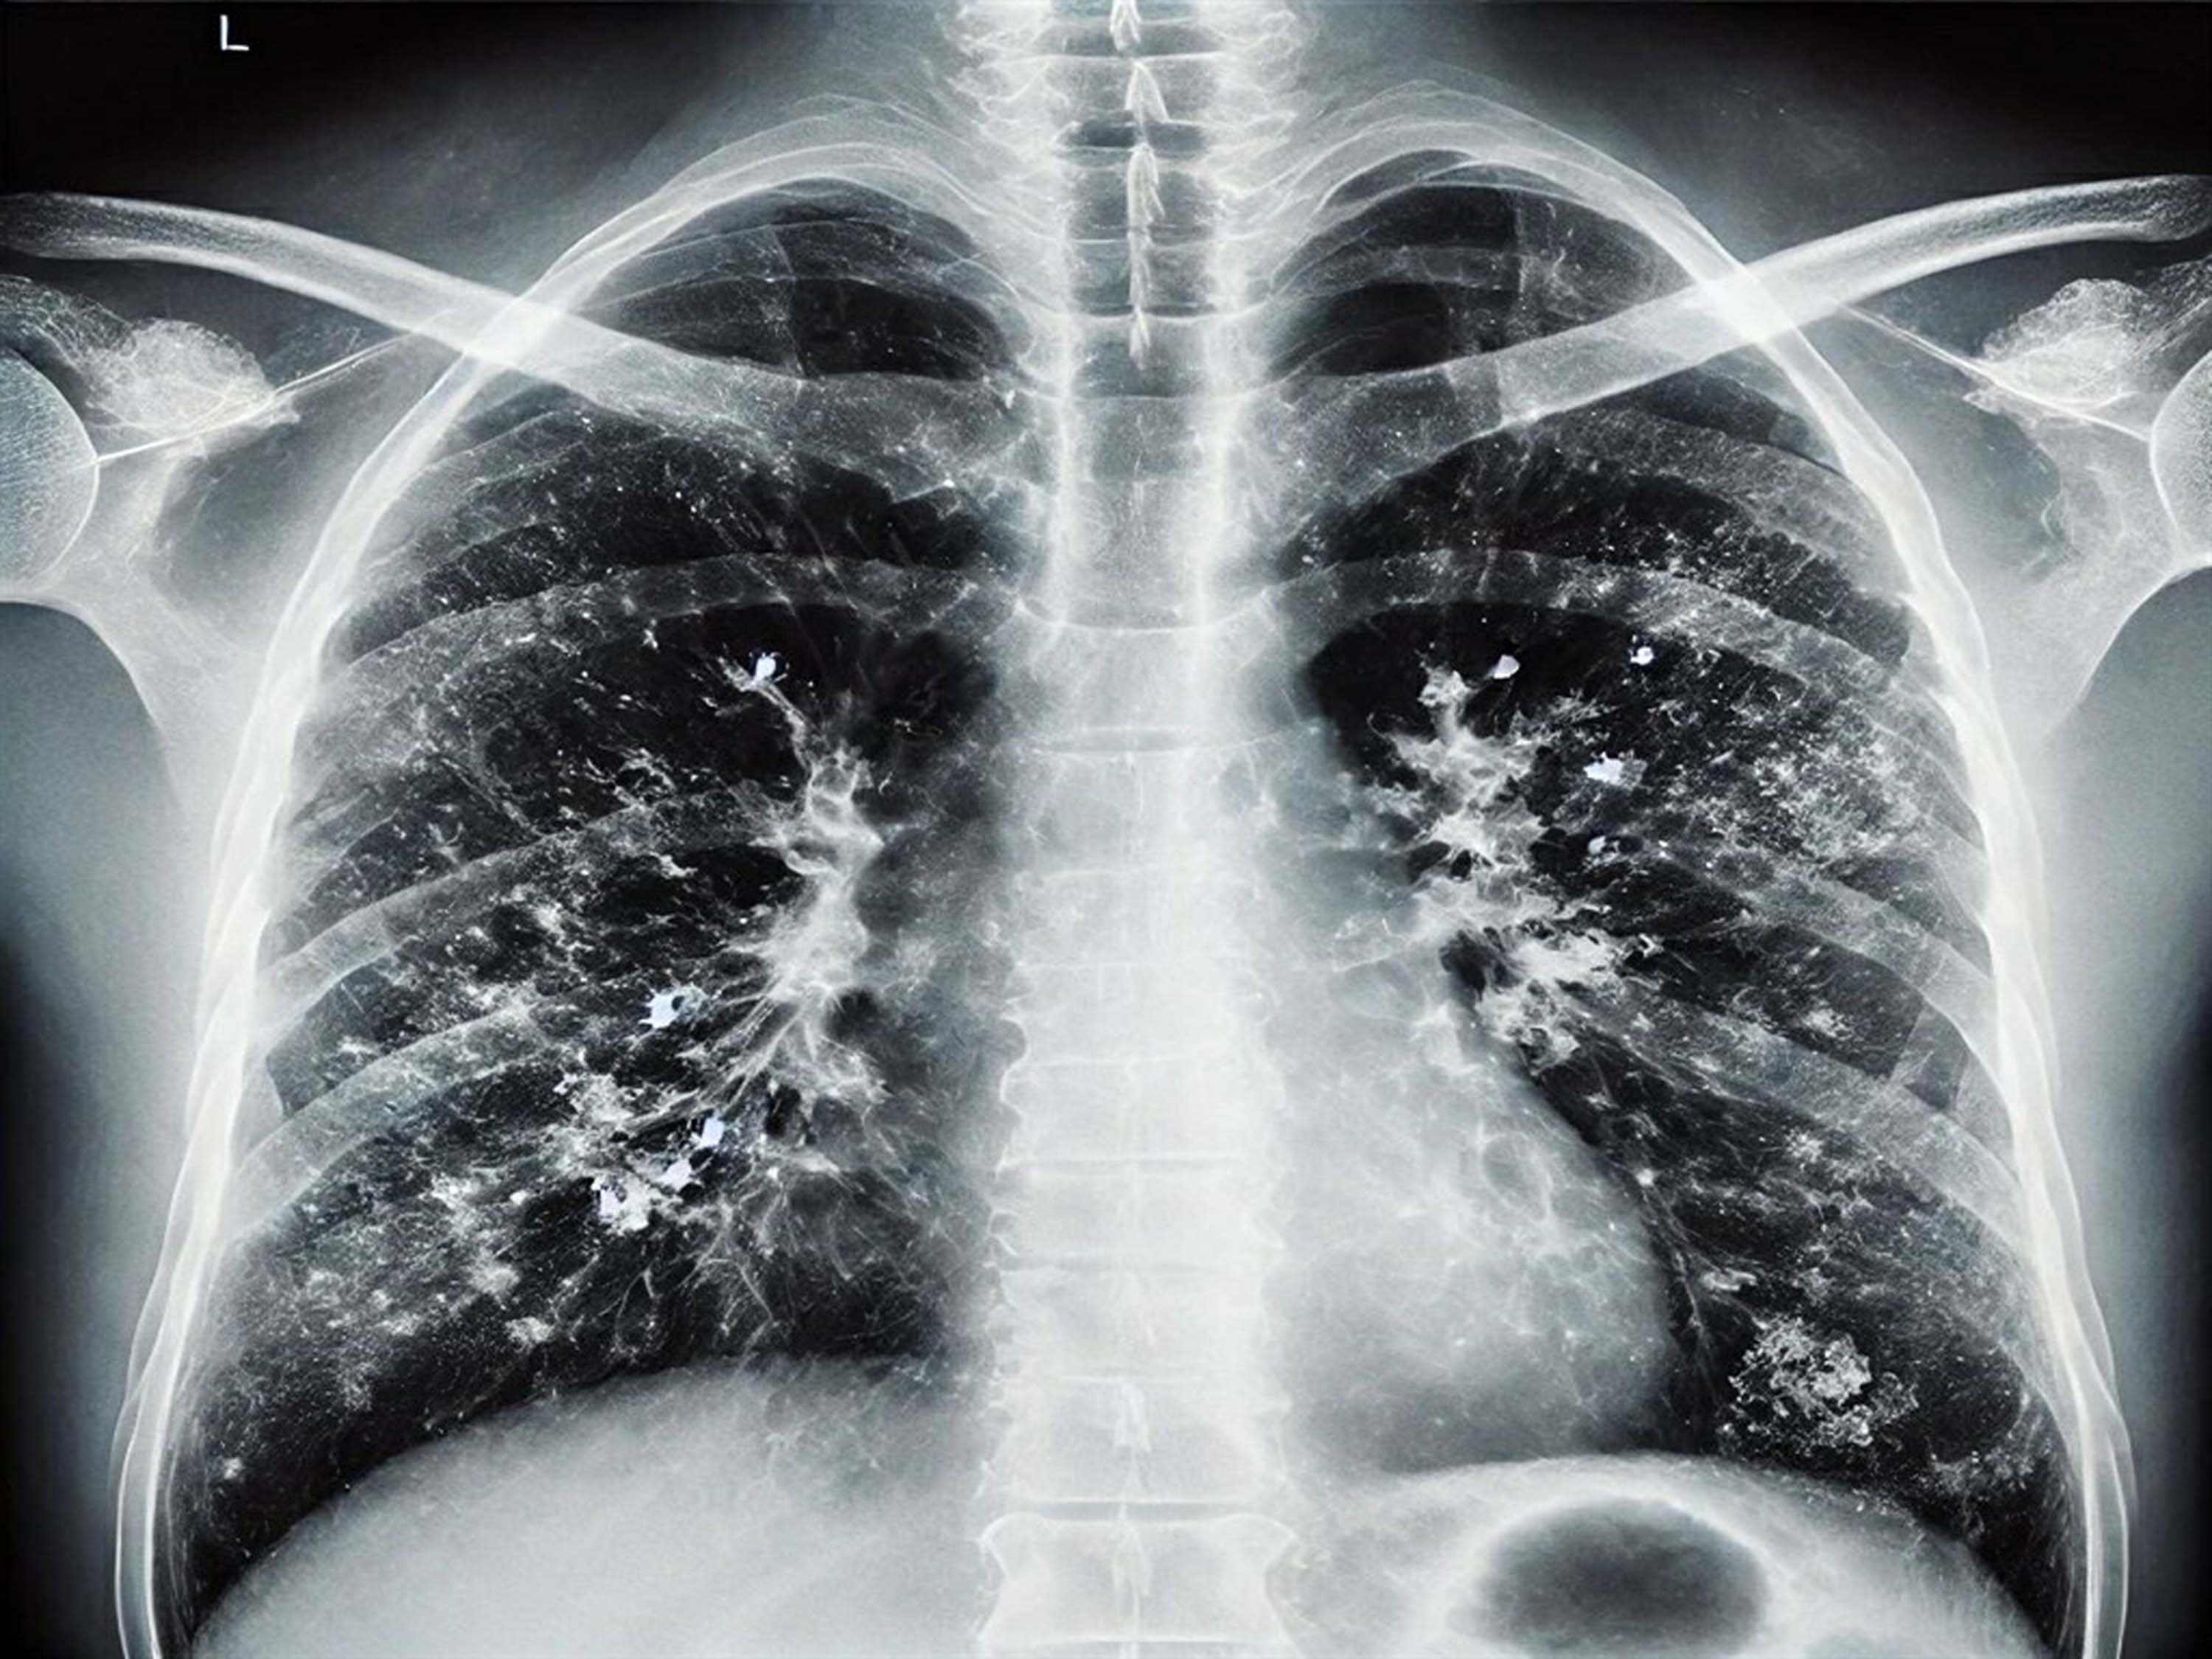

Kış aylarında görülen solunum yolu enfeksiyonu etkenlerinin tek bir virüse bağlı olmadığını, birden fazla etkenin dolaşımda olduğunu belirten Kızılelma, hastalığın seyrinin kişiden kişiye değişebileceğini söyledi. Enfeksiyona yakalanan kişilerin süreci en hafif şekilde atlatabilmesi için bol sıvı alması ve istirahat etmesi gerektiğini vurgulayan Kızılelma, "Dinlenmek, iyileşme sürecinin en önemli ilacıdır" dedi. Ancak belirtilerin ağırlaşması durumunda vakit kaybedilmemesi gerektiğini belirten Kızılelma, "Ateşin düşmemesi, şiddetli öksürük ve genel durum bozukluğu gibi durumlarda mutlaka bir hekime başvurulmalı ve profesyonel destek alınmalıdır" diyerek sözlerini noktaladı.